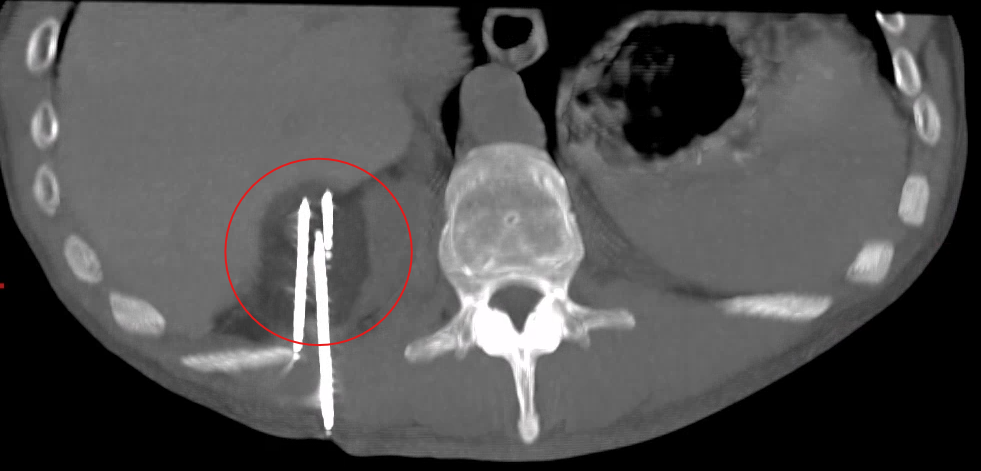

Computed Tomography (CT) for detailed cross-sectional imaging with precision needle placement

Our cancer care team provides targeted treatments including portacath insertion and troubleshooting, cryoablation, TACE, SIRT, and complex biopsy and drainage procedures—delivering cancer therapies directly to tumours while minimising impact on healthy tissue.